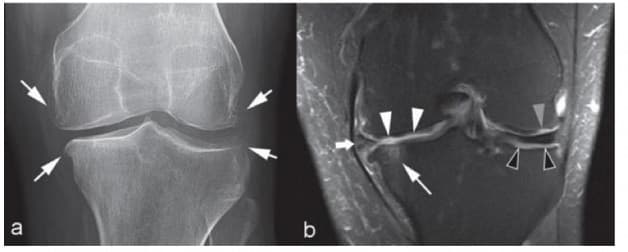

3.2 Bệnh lý dây chằng

Đứt dây chằng chéo cấp tính, tổn thương dây chằng mạn tính, đứt dây chằng chéo sau, tổn thương dây chằng bên chày,… có thể phát hiện được thông qua chụp cộng hưởng từ khớp gối.